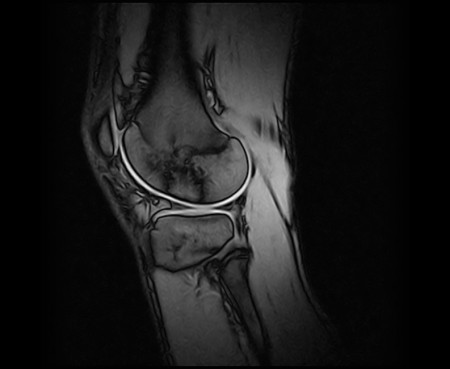

Porckopás a femur lateralis részén